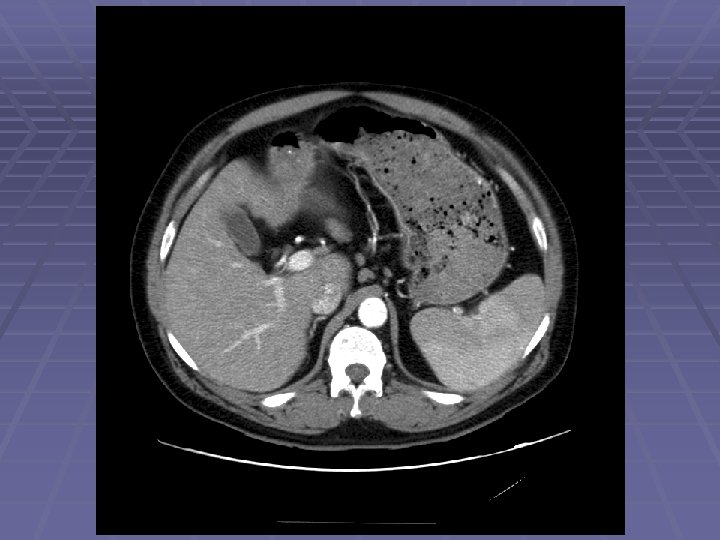

Liver Mass

FNA of Liver Mass

EUS Evaluation of Left Lobe of Liver